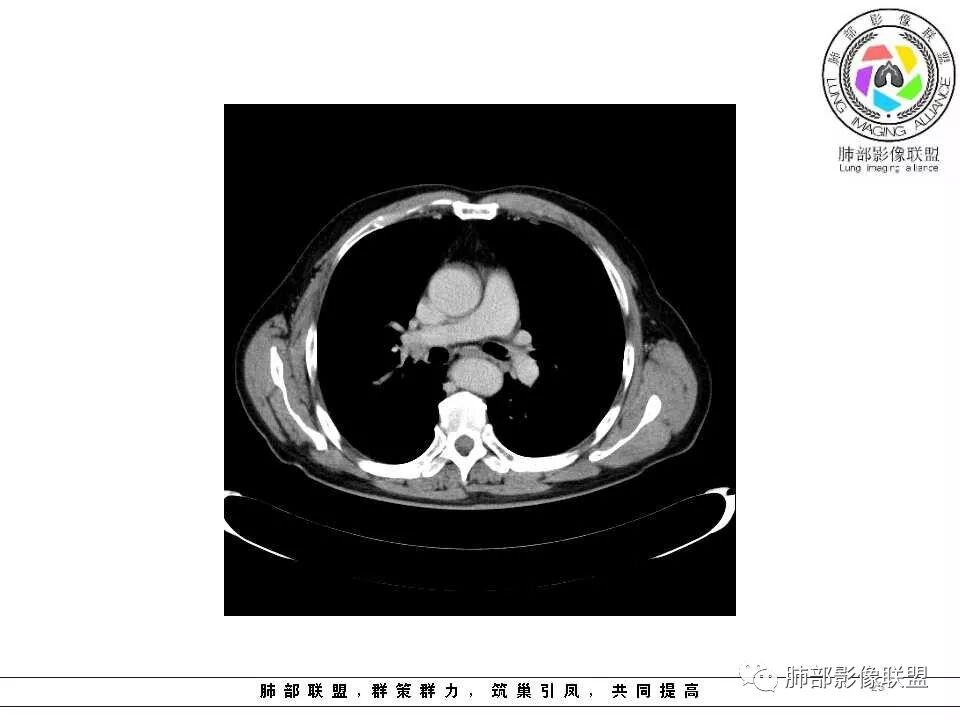

老年男性,两肺可见小叶中央型肺气肿,提示应该有抽烟史。2016年片,右肺门支气管稍模糊,考虑慢性感染,纵膈淋巴结稍大。但2017年左肺上叶新发占位,堵塞支气管,引起局部肺不张伴感染,且纵膈淋巴结较2016年变大,患者同时伴有咯血,考虑恶性。鳞癌?类癌?小细胞?

肺气肿背景,2016年左肺上叶上舌段见微结节,2017年5月左肺结节增大,密度均匀,边缘光滑锐利,与邻近血管关系密切,血管贴壁走行,外侧见尖状突起,下舌段片状影,沿着支气管走行,内有粘液栓,考虑鳞癌,鉴别小细胞肺癌。

肺气肿背景,2016年左肺上叶上舌段见微结节,一年后左肺结节增大,密度均匀,边缘光滑、膨隆,似见小分叶,下舌段片状影,沿着支气管走行,内,老年患者,咯血1月。考虑恶性病变并阻塞性肺炎,鳞癌?注意鉴别结核。

老年男性,咯血1月,肺气肿背景,16年左肺上叶舌段结节,左肺门疑似淋巴结肿大,呈结节感。17年左肺上叶舌段见沿支气管走行分布结节 远端阻塞性肺炎,左肺门淋巴结肿大明显,首先考虑恶性病变,鳞癌?类癌?

前次片2016年4月20相应位置就有小点状病灶,2017-5-15呈结节影改变,边界膨隆,远端阻塞炎性改变,考虑肺癌,鉴别炎性结节!

前后对比,这些结节其实是没引起支气管远端病变的

南大标注,这几个确实结节没有阻塞支气管,感觉是在血管分叉地方。

@南边 关键是上面这几个结节有的密度度,有的密度低。与下面堵塞支气管的结节样改变是否不是一回事,

如果下面堵塞是恶性,那上面的是不是考虑转移?另外一年结那个疑似结节的地方与现在堵塞的地方好象不一致。

后头看前片似乎当时腔内壁稍增厚一点

那就是说这是新发的